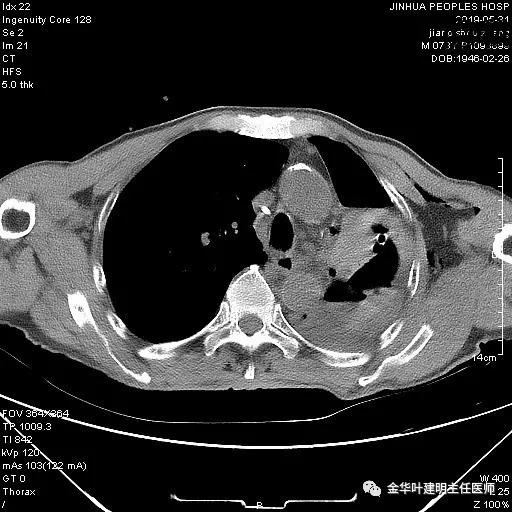

考虑左侧大量胸腔积液,遂进一步胸部CT检查:

以上是肺窗表现,下面为纵隔窗影像: